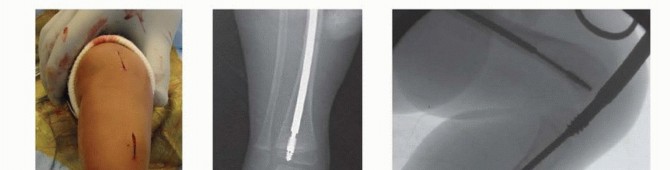

## For the femur, a 1.5-cm vertical incision is made, starting at the tip of the greater trochanter and extending proximally (FIG 7A).

## The tensor fascia is then incised, exposing the greater trochanter (FIG 7B).

FIG 7 • A. A 1.5-cm incision is made proximal to the greater trochanter. B. Greater trochanter is exposed.

## TECH FIG 1 • A. Guidewire placed through the greater trochanter to the site of the first osteotomy. B. Localization for osteotomy using C-arm. Reaming can be done at the site of the osteotomy to stabilize the proximal segment. C. A 1-cm incision is made over the apex of the osteotomy, and the soft tissues are spread to the periosteum. D. The osteotome is rotated and the osteotomy completed. Gentle manual traction and use of a lever such as a padded mallet will help to gently align and complete the osteotomy site. E. Guidewire in the distal femur.